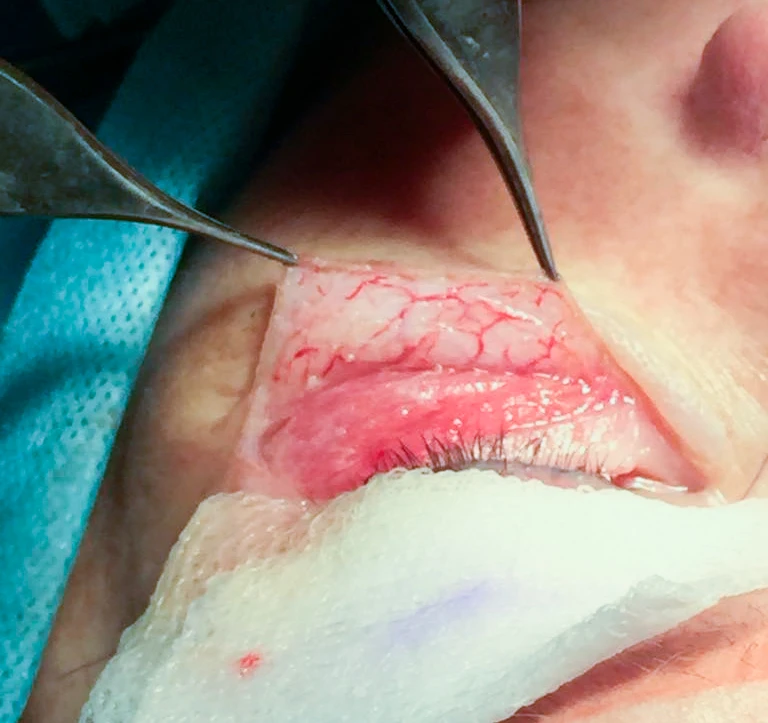

Лазерным лучом аппарата SmartXide2 DOT (фракционный лазер CO2) при использовании импульса DekaPulse (D-Pulse) с параметрами power 5.0 * 5 Гц был выполнен разрез (хирургической насадкой) кожи нижнего века от слезной точки, далее на расстоянии 2 мм от реснитчатого края до наружного угла глаза (на 0,5–1,0 см за наружный угол глаза) по средней борозде «гусиной лапки». Однослойный кожный лоскут в области нижнего века бережно отслаивался до необходимых границ, а именно до малярного жирового пакета, с полным сохранением сосудистой сетки (рис. 2а).

отделенный однослойный кожный лоскут

Рис. 2а. Показан отделенный однослойный кожный лоскут с сохраненной сеткой капиллярного кровеносного русла

Специфика лазерного импульса D-Pulse заключается в обеспечении тонкой прецизионной абляции ткани без латерального повреждения, при этом ее интенсивность и глубина регулируются независимо от фазы термической стимуляции. Именно эта уникальная возможность позволила выполнить минимально травматичную (атравматичную) диссекцию кожного лоскута в области нижнего века до необходимых границ, а именно до малярного жирового пакета, с полным сохранением сосудистой сетки (рис. 2а).